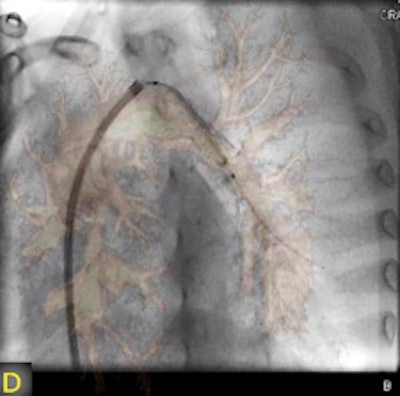

"The fusion of 3D reconstructions with live fluoroscopic images during catheterization may help to find the ideal fluoroscopic angulation during catheter-based interventions, to achieve difficult vascular crossings by the wire or the catheter, to choose the most appropriate material for catheterization, and to define and control optimized positioning of implants such as stents or valve prostheses," Glöckler and colleagues explained.

"One unique feature of FD-CT is the possibility of merging 3D reconstructions with the real-time fluoroscopic image," a potentially useful way to identify ideal C-arm angulations for achieving wire passage for atypical vascular crossings, and to optimally depict the implant position of coils, plugs, stents, and valves," Glöckler and colleagues wrote. "In fact, image fusion of 3D reconstructed FD-CT images with the live fluoroscopic image was frequently rated as 'very useful' (57.4%)."

A typical example is the visualization of the coronary arteries during transcatheter pulmonary valve implantation.